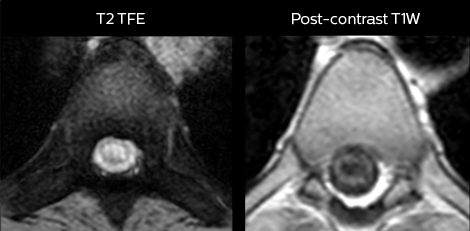

“We use mDIXON TSE extensively in our spine imaging in the emergency room,” says Dr. Karis. “It’s particularly nice in that it is very robust with regard to susceptibility type of problems that would come up with traditional spectral fat-saturated images; these problems are essentially eliminated with the mDIXON technique. In our ED environment it’s really nice to have the fat-free imaging that goes along with the mDIXON technique.

“For the thoracic and cervical spine routine non-contrast exam, for example, we perform one mDIXON T2 TSE sequence, which provides us with two outputs: the fat-and-water-together T2-weighted images, as well as the water-only sagittal T2-weighted images. And then we also perform an axial gradient echo exam.”

Cervical spine routine exam

This patient presented with headache that was worse with neck flexion and we see a Chiari 1 malformation with low-lying cerebellar tonsils as well as some degenerative cervical thrombolytic change.